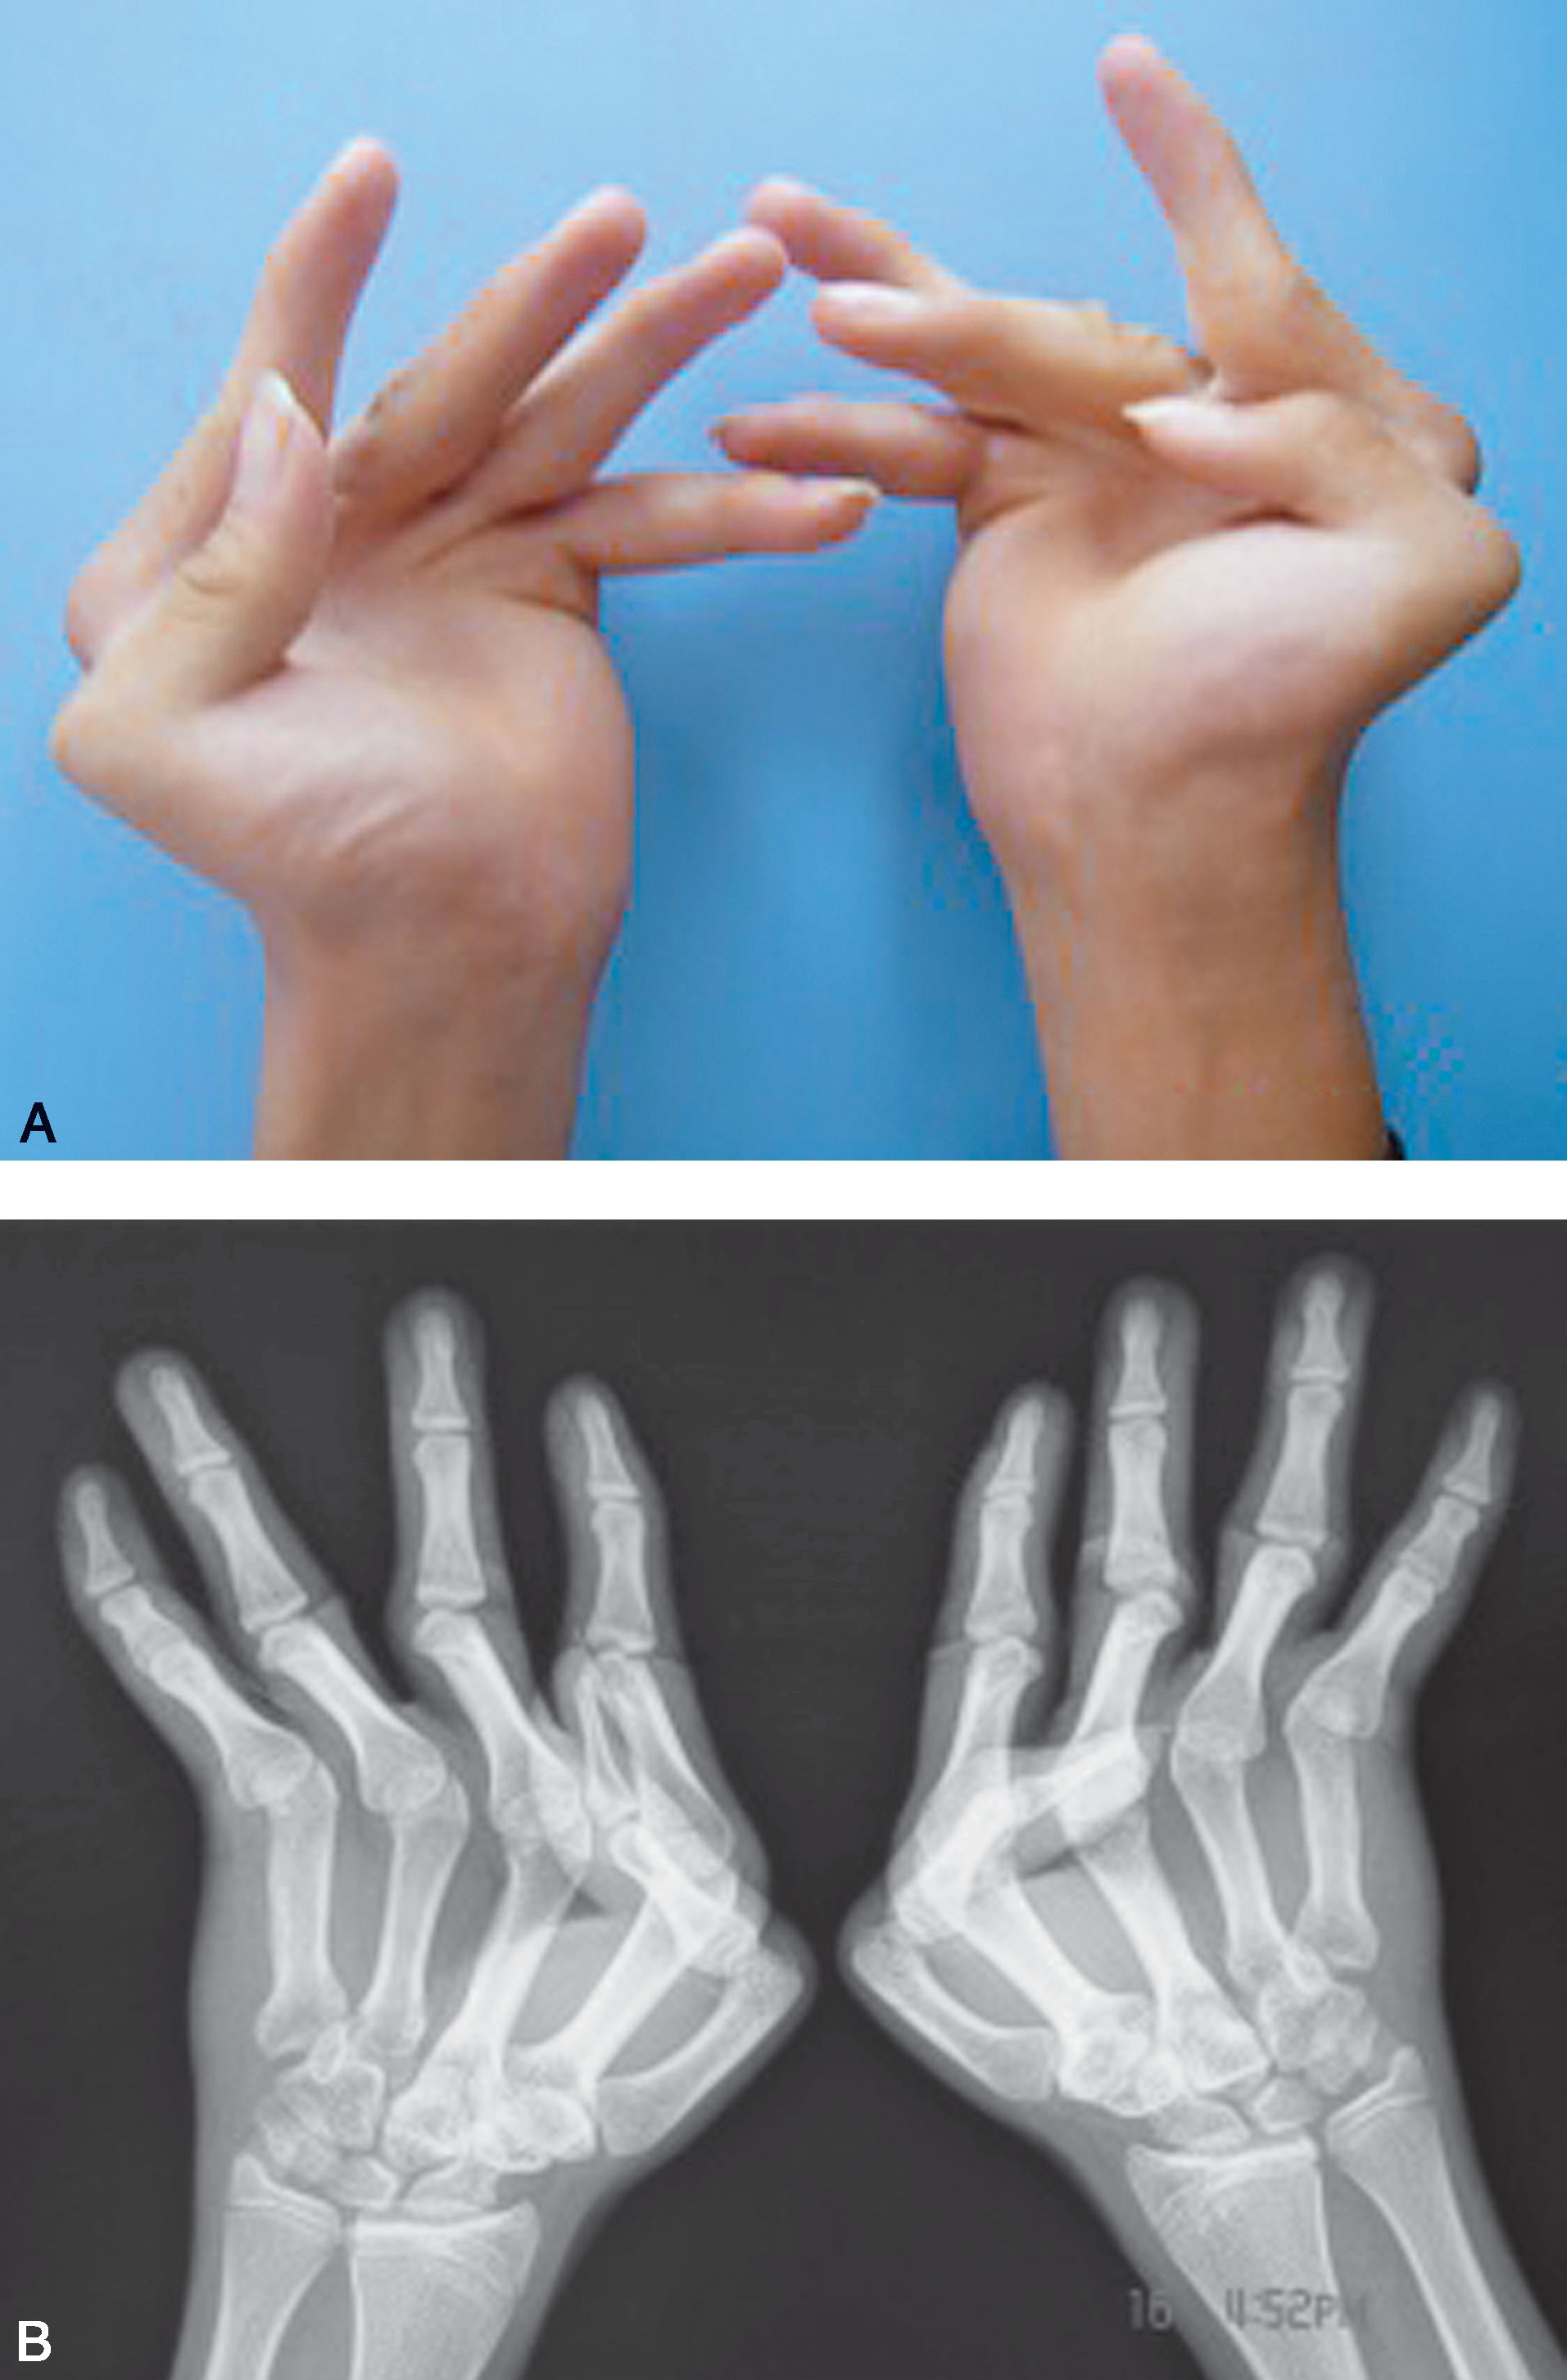

图1-2-7 右侧拇指发育不良及大鱼际缺如

A.右侧拇指发育不良,大鱼际缺如(侧面观);B.掌面观显示大鱼际缺如,拇指内收、旋后